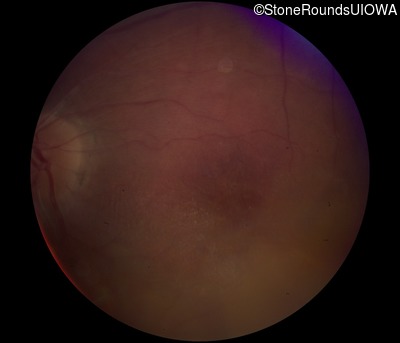

Fundus Photography - Right - 20/40 -2

Exemplar